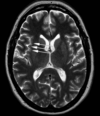

1

Q

A

quadrigeminal cistern

2

Q

A

left horizontal semi circular canal

3

Q

A

body of corpus callosum

4

Q

A

falx cerebri

5

Q

A

4th ventricle

6

Q

A

left posterior cerebral artery

7

Q

A

left posterior limb of internal capsule

8

Q

A

anterior clinoid process of sphenoid bone

9

Q

A

cingulate gyrus

10

Q

A

venous sinus confluence

aka torcula herophili